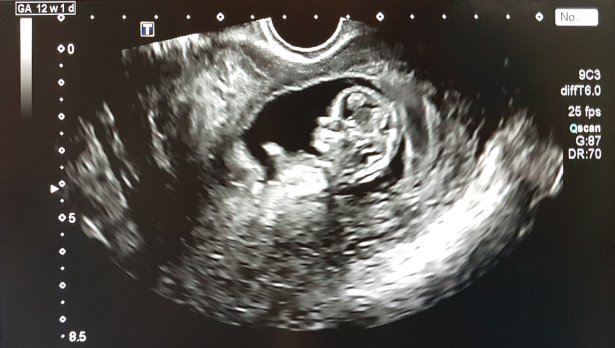

Очаква ли Азис бебе? Това се питат неговите фенове, след като той сподели любопитни кадри в социалните мрежи. В тях той показва бебе в корема на майка му, заснето от видеозон в гинекологичен кабинет.

В клипа на Азис бебето мърда в утробата, а на видеозона пише, че неговата майка е във втория триместър от бременността. Тя обаче остава неизвестна.

Неочакваното включване от лекарския кабинет накара последователите му да се замислят дали наистина бебето е негово или на някого от близкото му обкръжение.